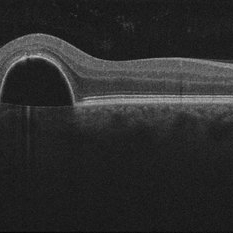

Aquired Vitelliform Maculopathy

Jun 29 2014 by John S. King, MD

Initial presentation.

Photographer: Wayne A Ladlee Jr

Imaging device: Cirrus

Condition/keywords: aquired vitelliform maculopathy